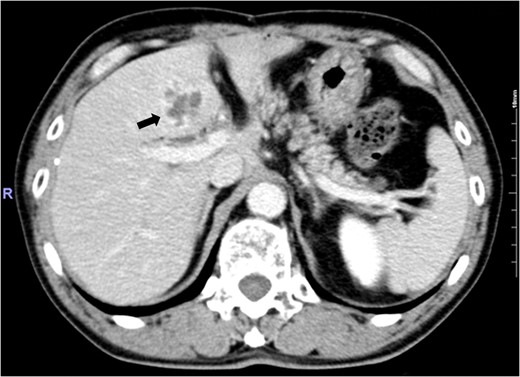

The patient was a 69-year-old man. In 2000, at 56 years of age, he had undergone PPPD (Imanaga procedure) for duodenum papilla cancer. Then, at the third year following surgery, the patient experienced fever several times per year and received conservative treatment for a diagnosis of cholangitis. He also developed liver abscess at the 10th year after surgery (Fig. 1). The patient was hospitalized 12 times in total for cholangitis until the 13th year following surgery. In late June 2013, he developed fever and epigastric pain several hours after dinner and was again hospitalized for suspected cholangitis. His temperature was 38.7°C. White blood cell count was 6.94 × 104/μl, aspartate aminotransferase, alanine aminotransferase, γ-glutamyl transpeptidase were within normal limits. Alkaline phosphatase, total bilirubin and C-reactive protein were mildly elevated to 328 U/l, 1.1 mg/dl and 4.19 mg/dl. Pneumobilia was observed on abdominal ultrasonography. Symptoms were immediately improved by fasting, antibiotics and conservative therapy with fluid replacement.

Abdominal enhanced computed tomography image showing an irregular ring-enhanced lesion in Segment 4 of the liver.